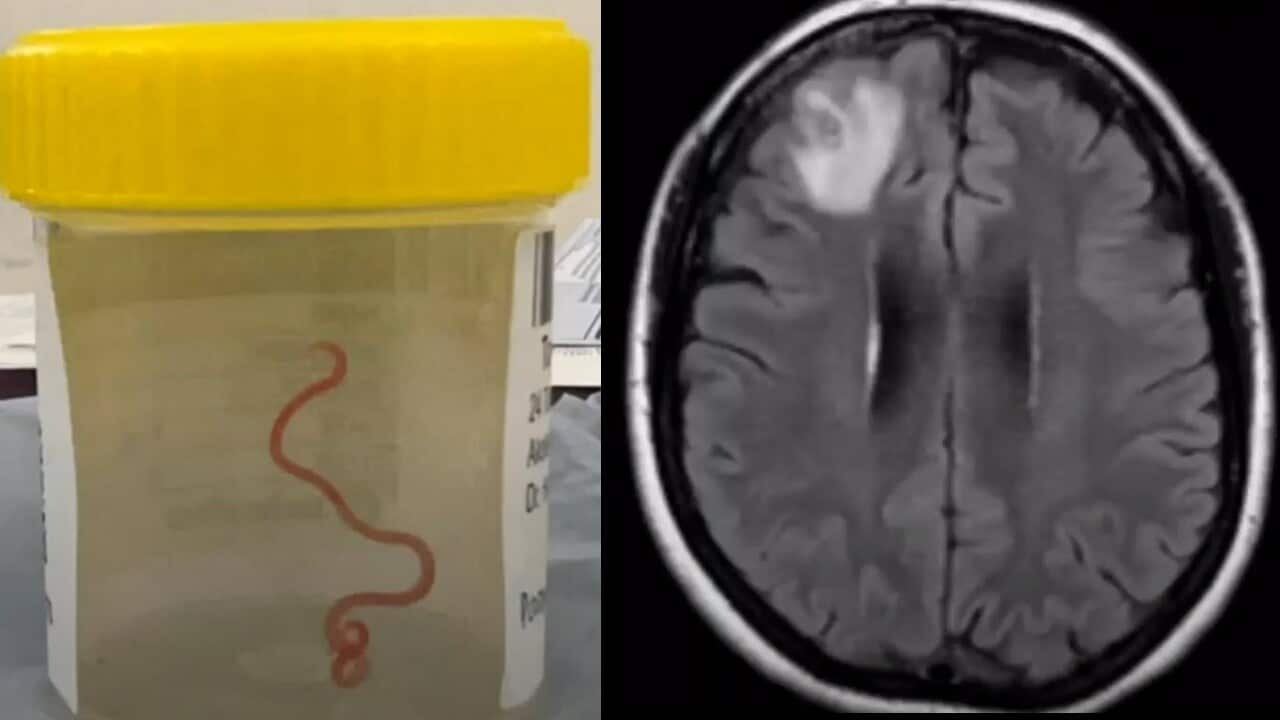

- కాన్బెర్రాలోని ఒక స్త్రీ మెదడు లో కనుగొన్న 8 cms parasitic roundworm